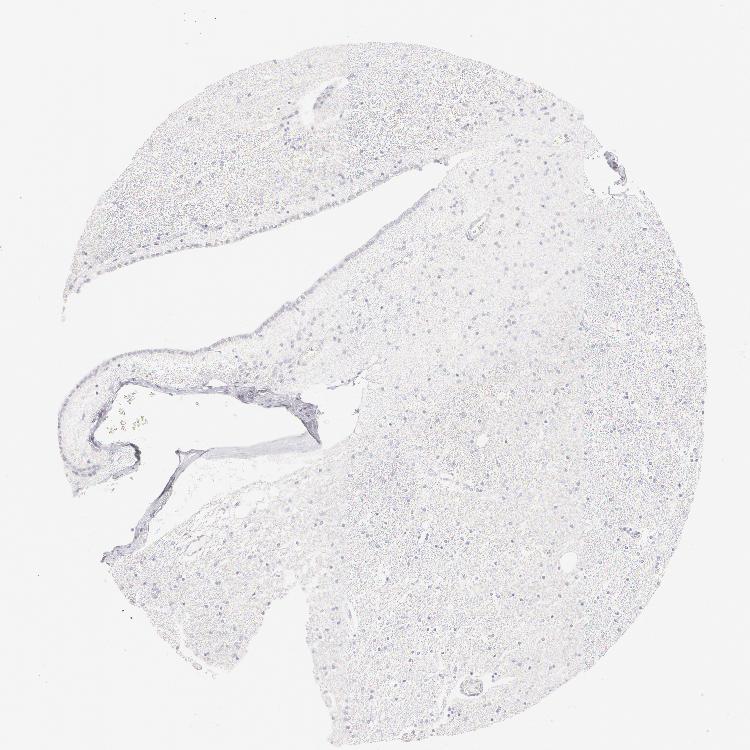

HIPPOCAMPUS - Antibody stainingi

Antibody staining in the annotated cell types in the current human tissue is reported as not detected, low, medium, or high, based on conventional immunohistochemistry profiling in selected tissues. This score is based on the combination of the staining intensity and fraction of stained cells.

Each image is clickable and will lead to virtual microscopy that enables deeper exploration of all samples and also displays staining intensity scores, fraction scores and subcellular localization as well as patient and tissue information for each sample.

Antibody HPA049866Antibody CAB000131Antibody CAB001696

Glial cells Not detectedNot detectedNot detected

Neuronal cells Not detectedNot detectedNot detected